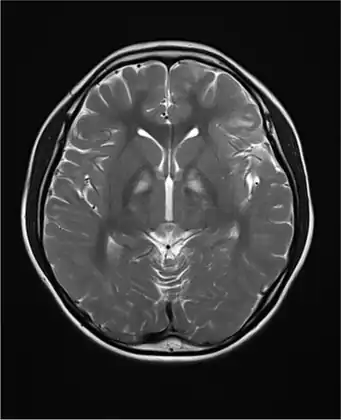

Brain MRI indicated diffuse demyelinating lesions in white matter of both cerebral hemispheres -